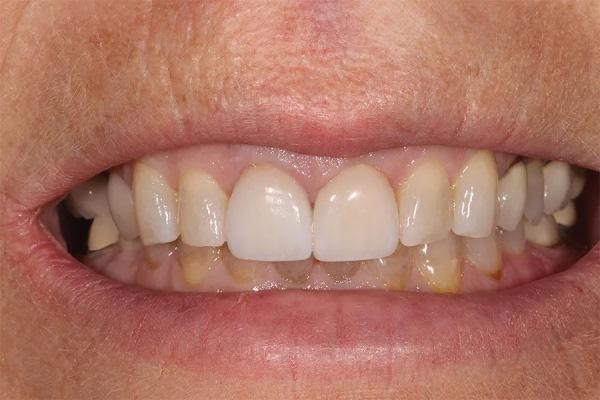

Пациентка, 58 лет, стоматолог-гигиенист, обратилась с жалобами на повторяющиеся неудачи реставрационного лечения. Она испытывала неудовлетворенность своим внешним видом (фото 1–3) и хотела получить более гармоничную, симметричную улыбку с более светлым оттенком зубов и меньшей выраженностью десневой улыбки. Будучи специалистом в области стоматологии, она понимала ограничения лечения отдельных зубов и, после многих лет разочарования, обратилась за комплексным долгосрочным решением, способным обеспечить стабильность, улучшить эстетику и предотвратить дальнейшее разрушение.

Фото 1. Улыбка анфас до лечения. Отмечается десневая улыбка.

Фото 2. Крупный план улыбки до лечения, демонстрирующий несоответствие реставраций в различных участках зубного ряда.